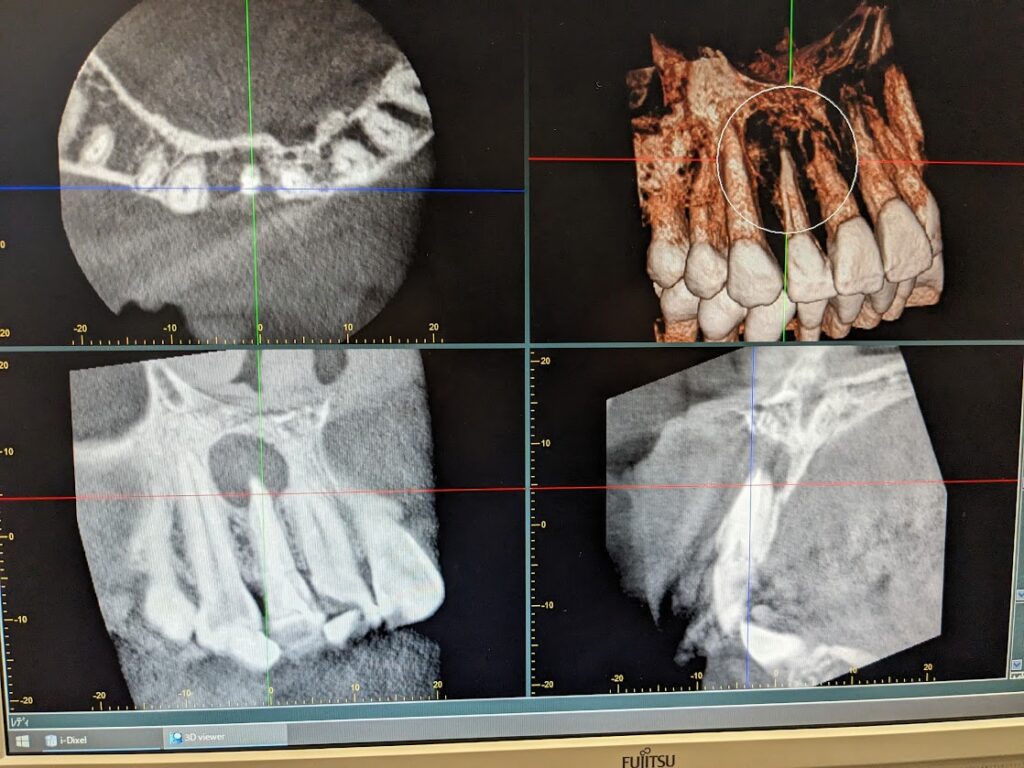

CTに頬側の皮質骨は完全に消失しており、鼻腔底に向かって進展していることを疑わせる拇指頭大の透過像を認めます。幸い口蓋側の骨にまで病巣は進展しておりませんでした。患者様に現在の状況と当院での治療方針、予後についてご説明いたしました。